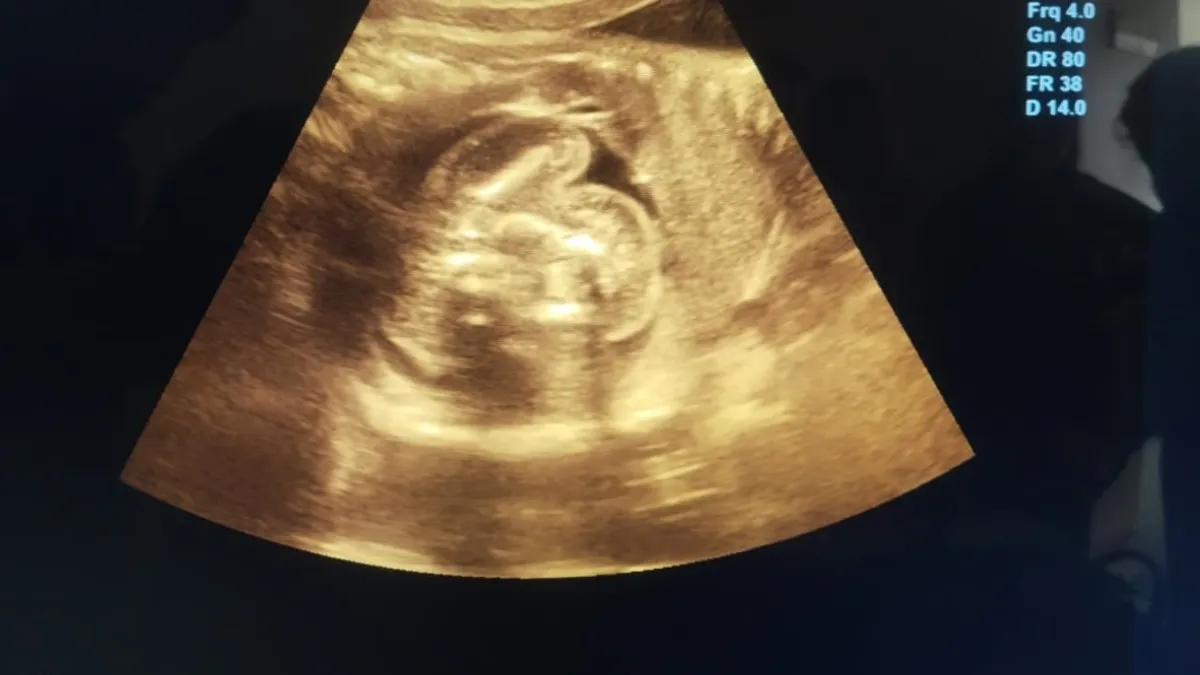

बुलंदशहर में महिला के गर्भाशय की जगह लीवर में पल रहा था बच्चा ,जांच हुई तो डॉक्टरों के उड़े होश

बुलंदशहर की एक महिला के लीवर में 12 हफ्ते का भ्रूण मिला, जो मेडिकल जगत के लिए हैरान कर देने वाला मामला है. डॉक्टरों के मुताबिक यह भारत में अपनी तरह का पहला और दुनिया में बेहद दुर्लभ केस है।

एमआरआई रिपोर्ट में पता चला की महिला प्रग्नेंट तो हैं लेकिन उसका गर्भाशय यानी यूट्रस खाली है. हैरानी की बात ये थी कि 12 हफ्ते का गर्भ उसके गर्भाशय में नहीं, बल्कि लीवर के दाहिने हिस्से में पल रहा था. गर्भ में धड़कन भी थी, यानी भ्रूण पूरी तरह से ज़िंदा था.